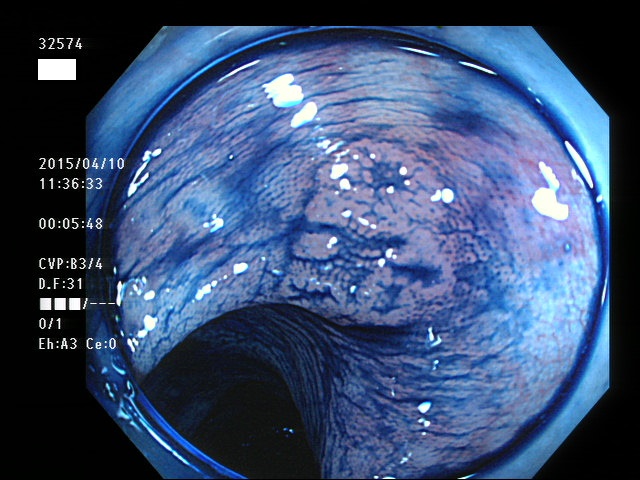

上記100名より抽出した平坦・陥凹型腺腫(=癌化の危険が高いが見落としやすい病変)の内視鏡写真

32573 32574 32575 32576 32577 32582 32583 32584 32585 32588 32593 32594